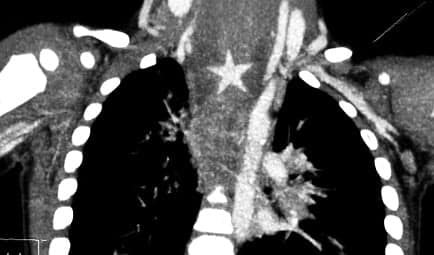

Eventually, an x-ray computed tomography scan (CT) revealed the real source of the problem: a plastic Christmas star, 18 millimetres in diameter.

Eventually, an x-ray computed tomography scan (CT) revealed the real source of the problem: a plastic Christmas star, 18 millimetres in diameter.